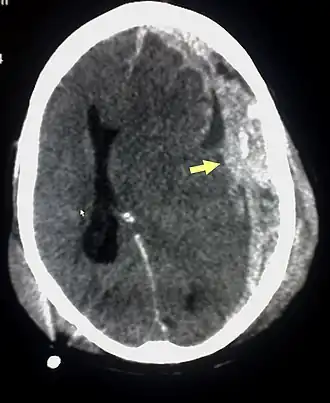

Le diagnostic se fait au scanner sans injection. Son accès est facile dans les pays développés. Il n'existe pas de contre-indication (sauf la grossesse).

Sur le scanner crânien, fait sans injection de produit de contraste, l'hématome sous-dural se présente habituellement sous une forme de croissant, dont la concavité suit la courbe du cerveau, stoppé seulement par les réflexions durales telles que la faux du cerveau et le tentorium. Cependant ils peuvent avoir une forme convexe, spécialement tout au début du saignement, ce qui peut les faire confondre avec les hémorragies épidurales (hématome extradural). Le sang peut être vu comme une densité stratifiée tout au long du tentorium. Dans les cas chroniques, on peut voir l'effacement des sillons ou le déplacement médian de la jonction substance blanche/substance grise, mais le sang peut avoir une densité très proche de celle du tissu cérébral (isodense), ce qui peut masquer l'hématome.

Les hématomes sous-duraux sont plus fréquents dans les parties supérieure et latérales du frontal et au niveau des lobes pariétaux[5],[12] ainsi que dans la fosse postérieure proche de la faux du cerveau et de la tente du cervelet[5].